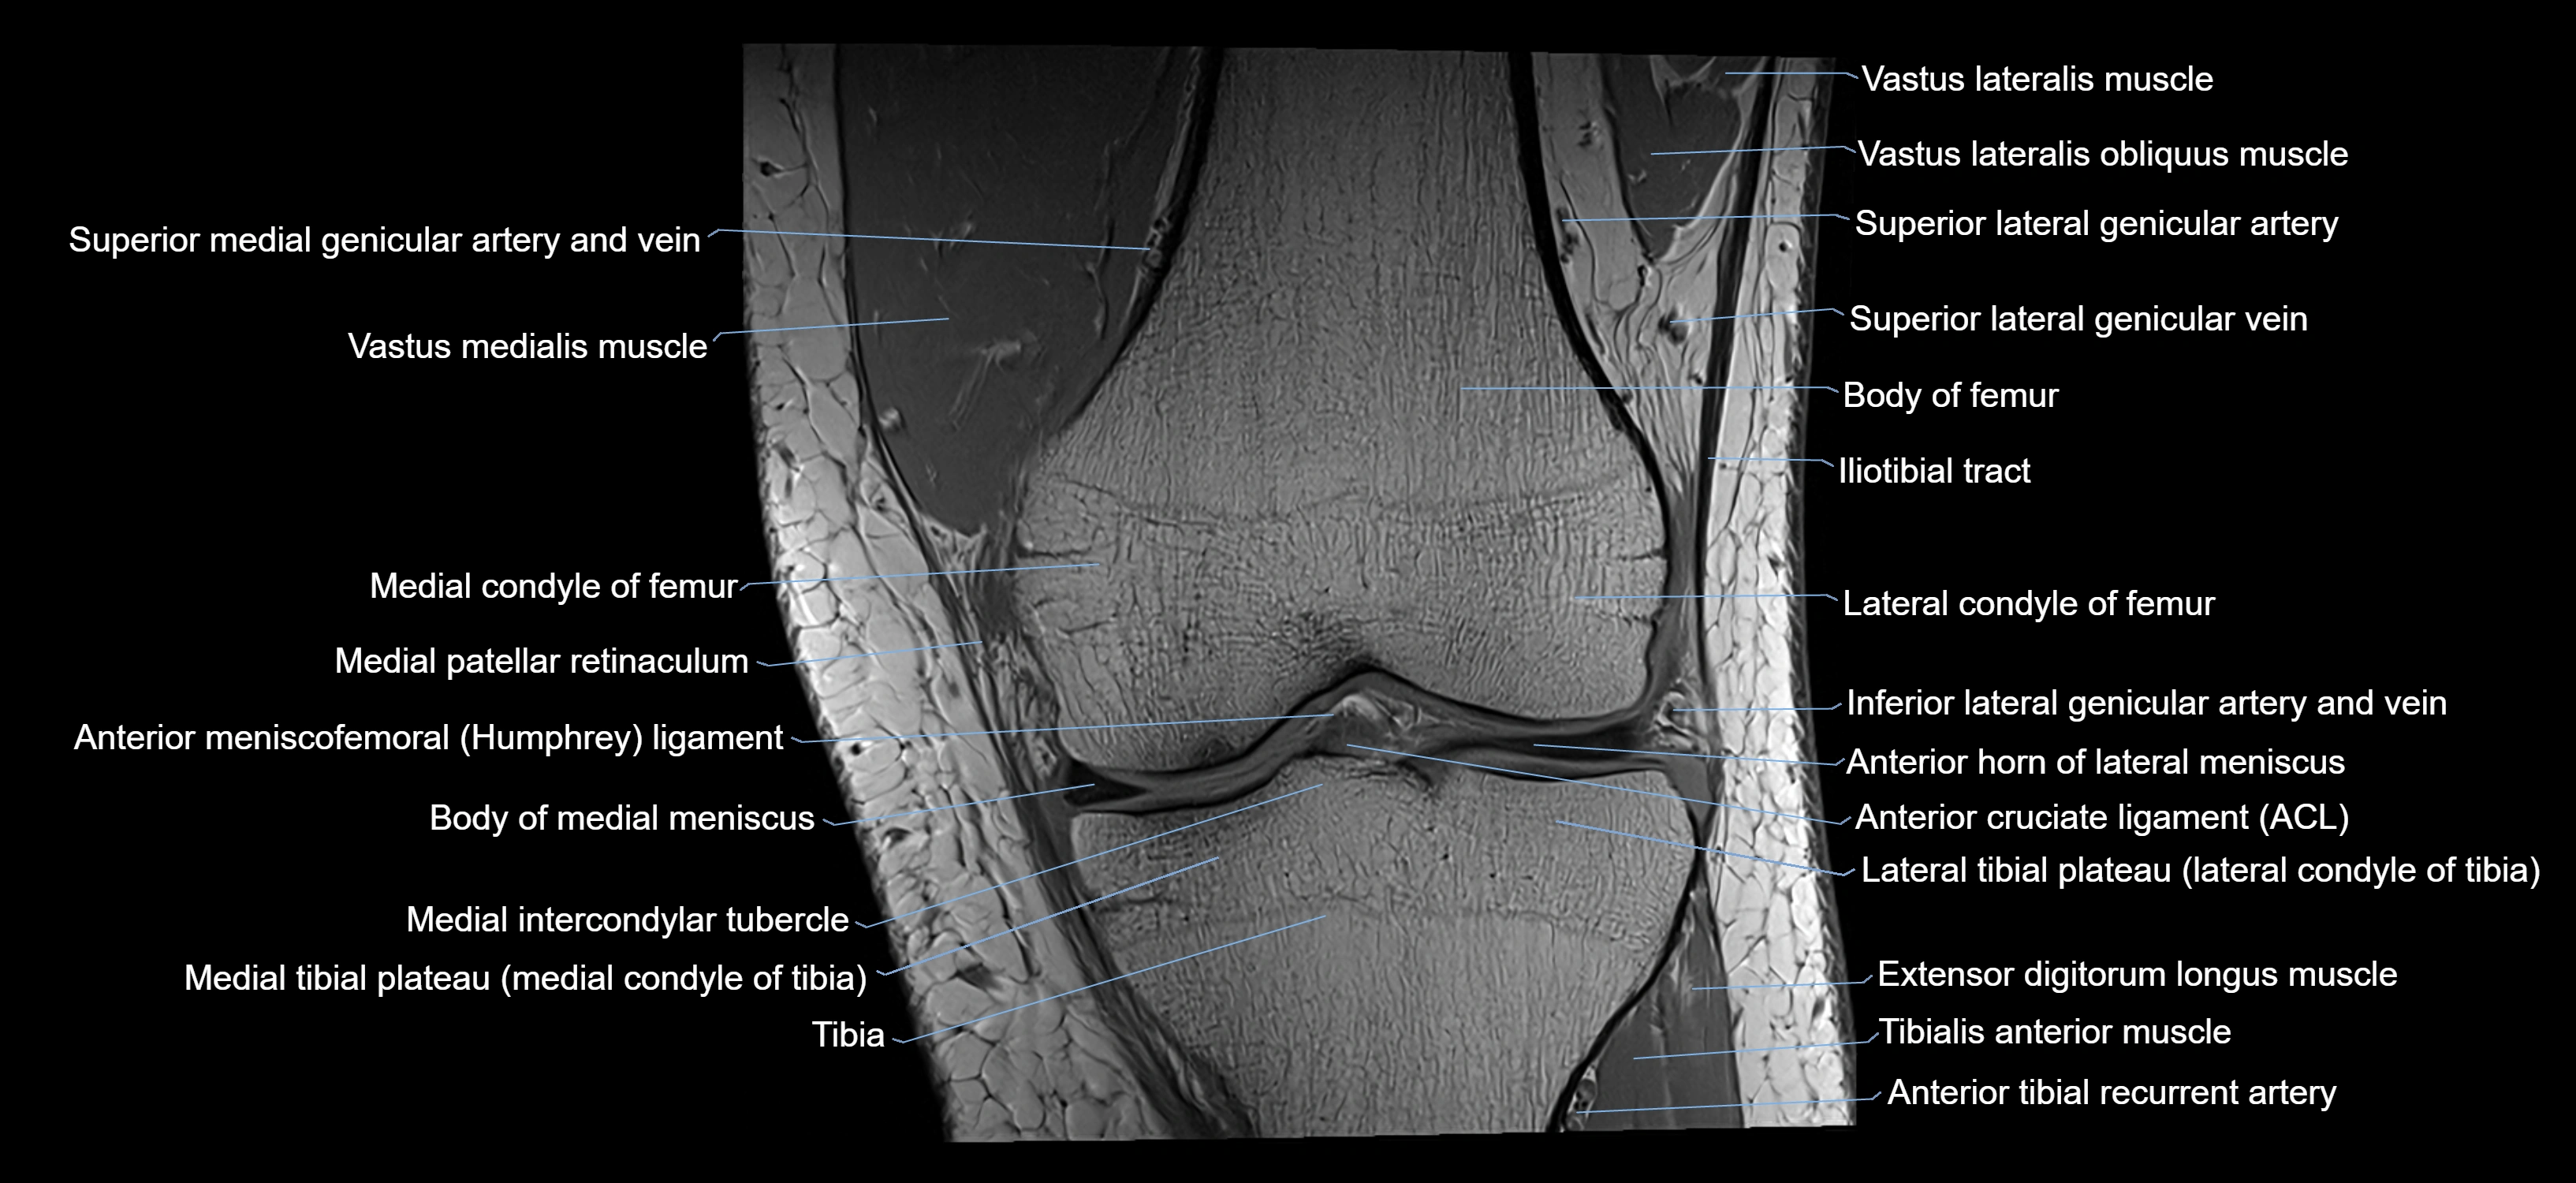

- Anterior cruciate ligament

- Anterior horn of lateral meniscus

- Body of medial meniscus

- Knee Joint

- Lateral condyle of femur

- Lateral condyle of tibia

- Medial condyle of femur

- Medial condyle of tibia

- Medial intercondylar tubercle

- Medial patellar retinaculum

- Medial tibial plateau

- Superior lateral genicular artery

- Superior lateral genicular vein

- Tibia

- Tibialis anterior muscle

- Vastus lateralis muscle